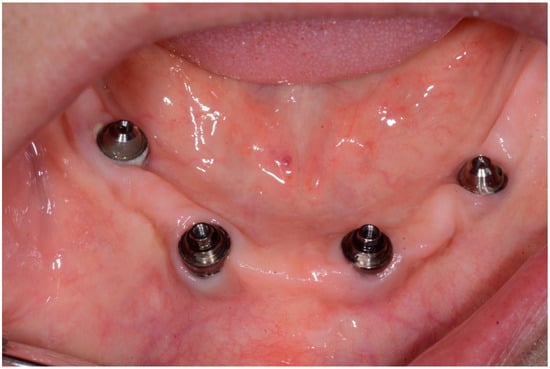

The patient showed a prosthetic rehabilitation on four implants (All-on-4®) of the lower and upper jaw. Implants were placed 8 years before, in the same Dental Clinical Department.

After removing the prosthetic rehabilitations, diagnosis of the soft tissue was done. Peri-implant assessment (PPD, TL, BI, PI, and mobility) and, subsequently, assessment of color, contour, consistency of soft tissues was performed. Individual oral hygiene instructions including re-education and motivation if needed was done. Bidimensional radiographic assessment (with periapical and panoramic radiograph) was performed (Figure 10 and Figure 11).

Figure 10.

X-ray of 3.5 dental implant in patient before treatment.

Figure 11.

X-ray of 4.5 dental implant in patient before treatment.